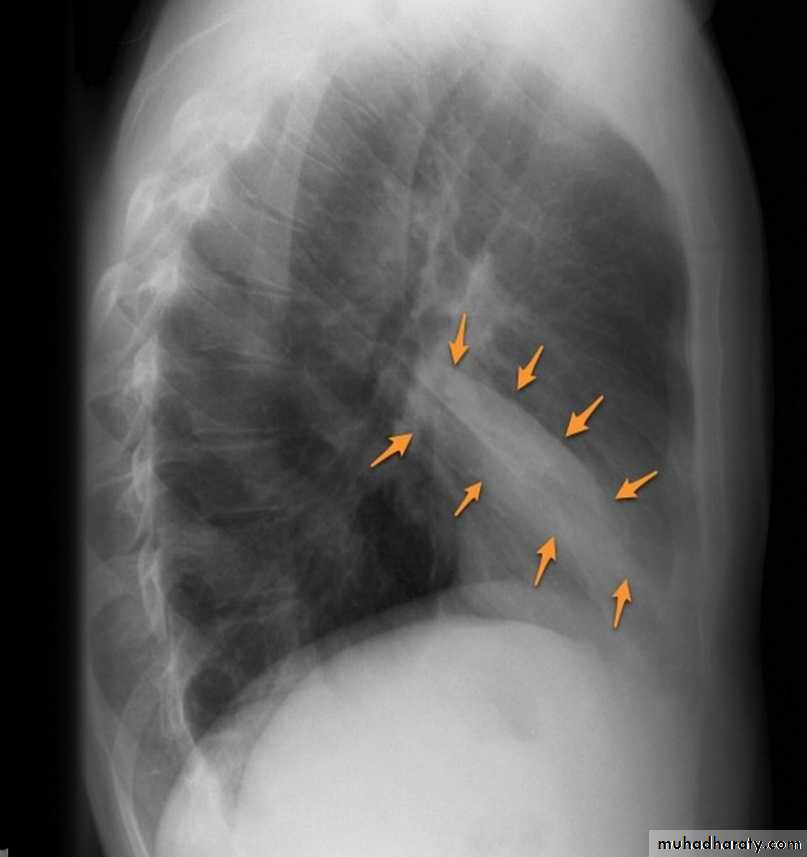

The oblique fissures are often seen on a normal lateral view .

Lobes and fissures

This cut-out of a lateral chest x-ray shows the positions of the lobes of the right lung

On the left the oblique fissure is in a similar position but there is usually no horizontal fissure, and so there are only two lobes on the left.

Right middle lobe collapse has distinctive features, and is usually relatively easily identified.

Radiographic features

Chest radiograph

Frontal chest XR showing opasity cause obscuration of the RT cardiac border

Lateral chest XR film the opacity is tongue like shape

versus (triangular in shape) in RT middle lobe consolidation seen in lateral chest XR film